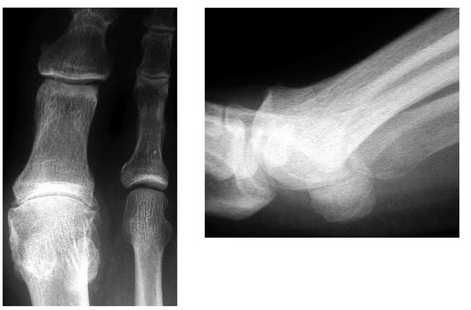

Рентгенограмма стопы в прямой проекции профессионального футболиста с признаками выраженной миграции сесамовидных костей.